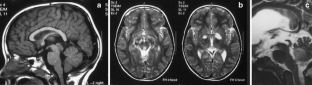

Bateman GA (2007) Magnetic resonance imaging quantification of compliance and collateral flow in late-onset idiopathic aqueductal stenosis: venous pathophysiology revisited. J Neurosurg 107:951–958

Fukuhara T, Luciano M (2001) Clinical features of late-onset idiopathic aqueductal stenosis. Surg Neuro 55:132–137

Stoquart-El Sankari S, Lehmann P, Gondry-Jouet C, Fichten A, Godefroy O, Meyer ME, Baledent O (2009) Phase-contrast MR imaging support for the diagnosis of aqueductal stenosis. AJNR Am J Neuroradiol 30:209–214